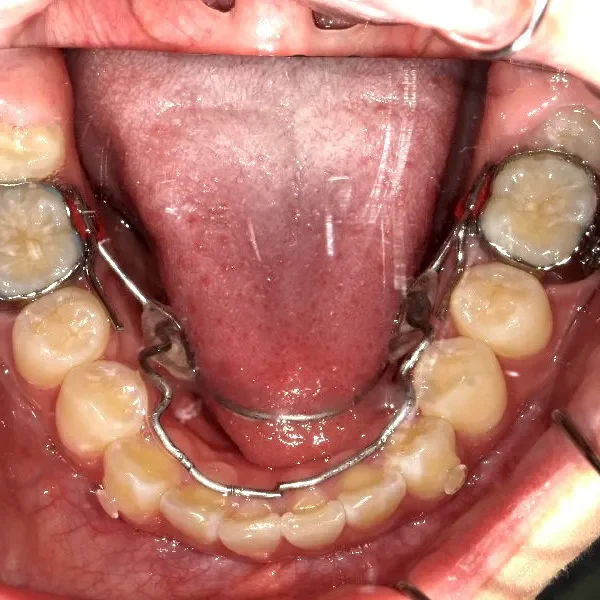

治療回数43回、7年4ヶ月の治療期間で矯正治療を終了しました。

主訴が改善され、ご満足頂きました。

治療終了後